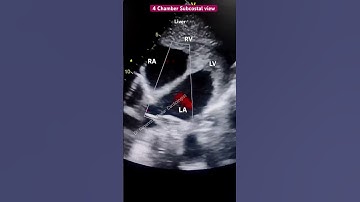

Subcostal view Echo for beginners #echo #shorts